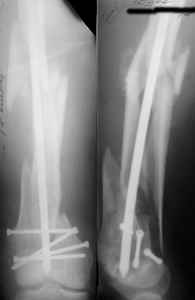

Attached are few examples from our Hospital:

A. Difficult reductions, even in retrograde nailing (my preference, easier control of "small" distal fragment) and it is much, much harder to do it anterograde (Alex, do you have one good case in your collection of anterograde nailing in very distal fractures - as you have suggested that I

should have done it in my previously posted case?

Malpositioning is much too common (recurvatum, varus - valgus).

B. Fixation loosening: distal cutting of the nail, non-unions do happen (cases attached).

Locking Plating has more distal screws than any nail, fixed angles and provides much better fixation, especially in osteoporotic bone.

I presented a series of ~25 such cases at EuroTrauma'2004. Many cases were discussed here. I attach am example. Look also recent cases at http://www.hwbf.org/hwb/conf/alex58/scfx.htm,

http://www.hwbf.org/hwb/conf/alex63/alex63.htm